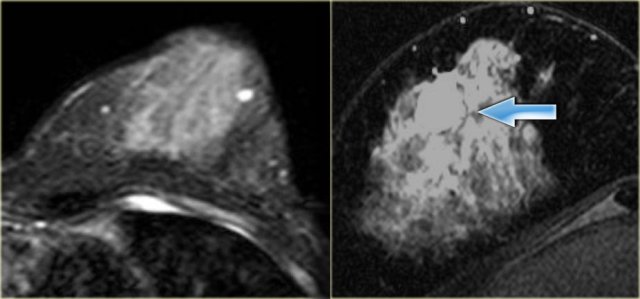

On the left two cases.

The image on the far left is an invasive ductal carcinoma presenting as a large, heterogeneously enhancing mass.

Next to it an example of an invasive ductal carcinoma presenting as a smaller mass with rim-enhancement.